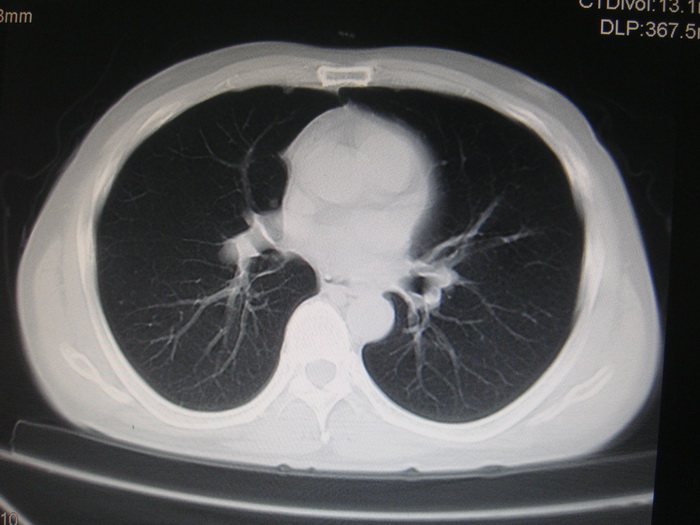

标题: CT28366:男性,45岁,偶尔发现右颈部肿块行胸部CT扫描。 [打印本页]

男性,45岁,偶尔发现右颈部肿块行胸部ct扫描。

两肺多发结节灶及纵膈淋巴结肿大考虑为转移

两肺多发性转移瘤,纵隔淋巴结转移。

两肺多发性转移瘤,纵隔淋巴结转移。食道中上段管壁似乎增厚,作相关检查。

两肺多发性转移瘤,前上纵隔淋巴结转移。